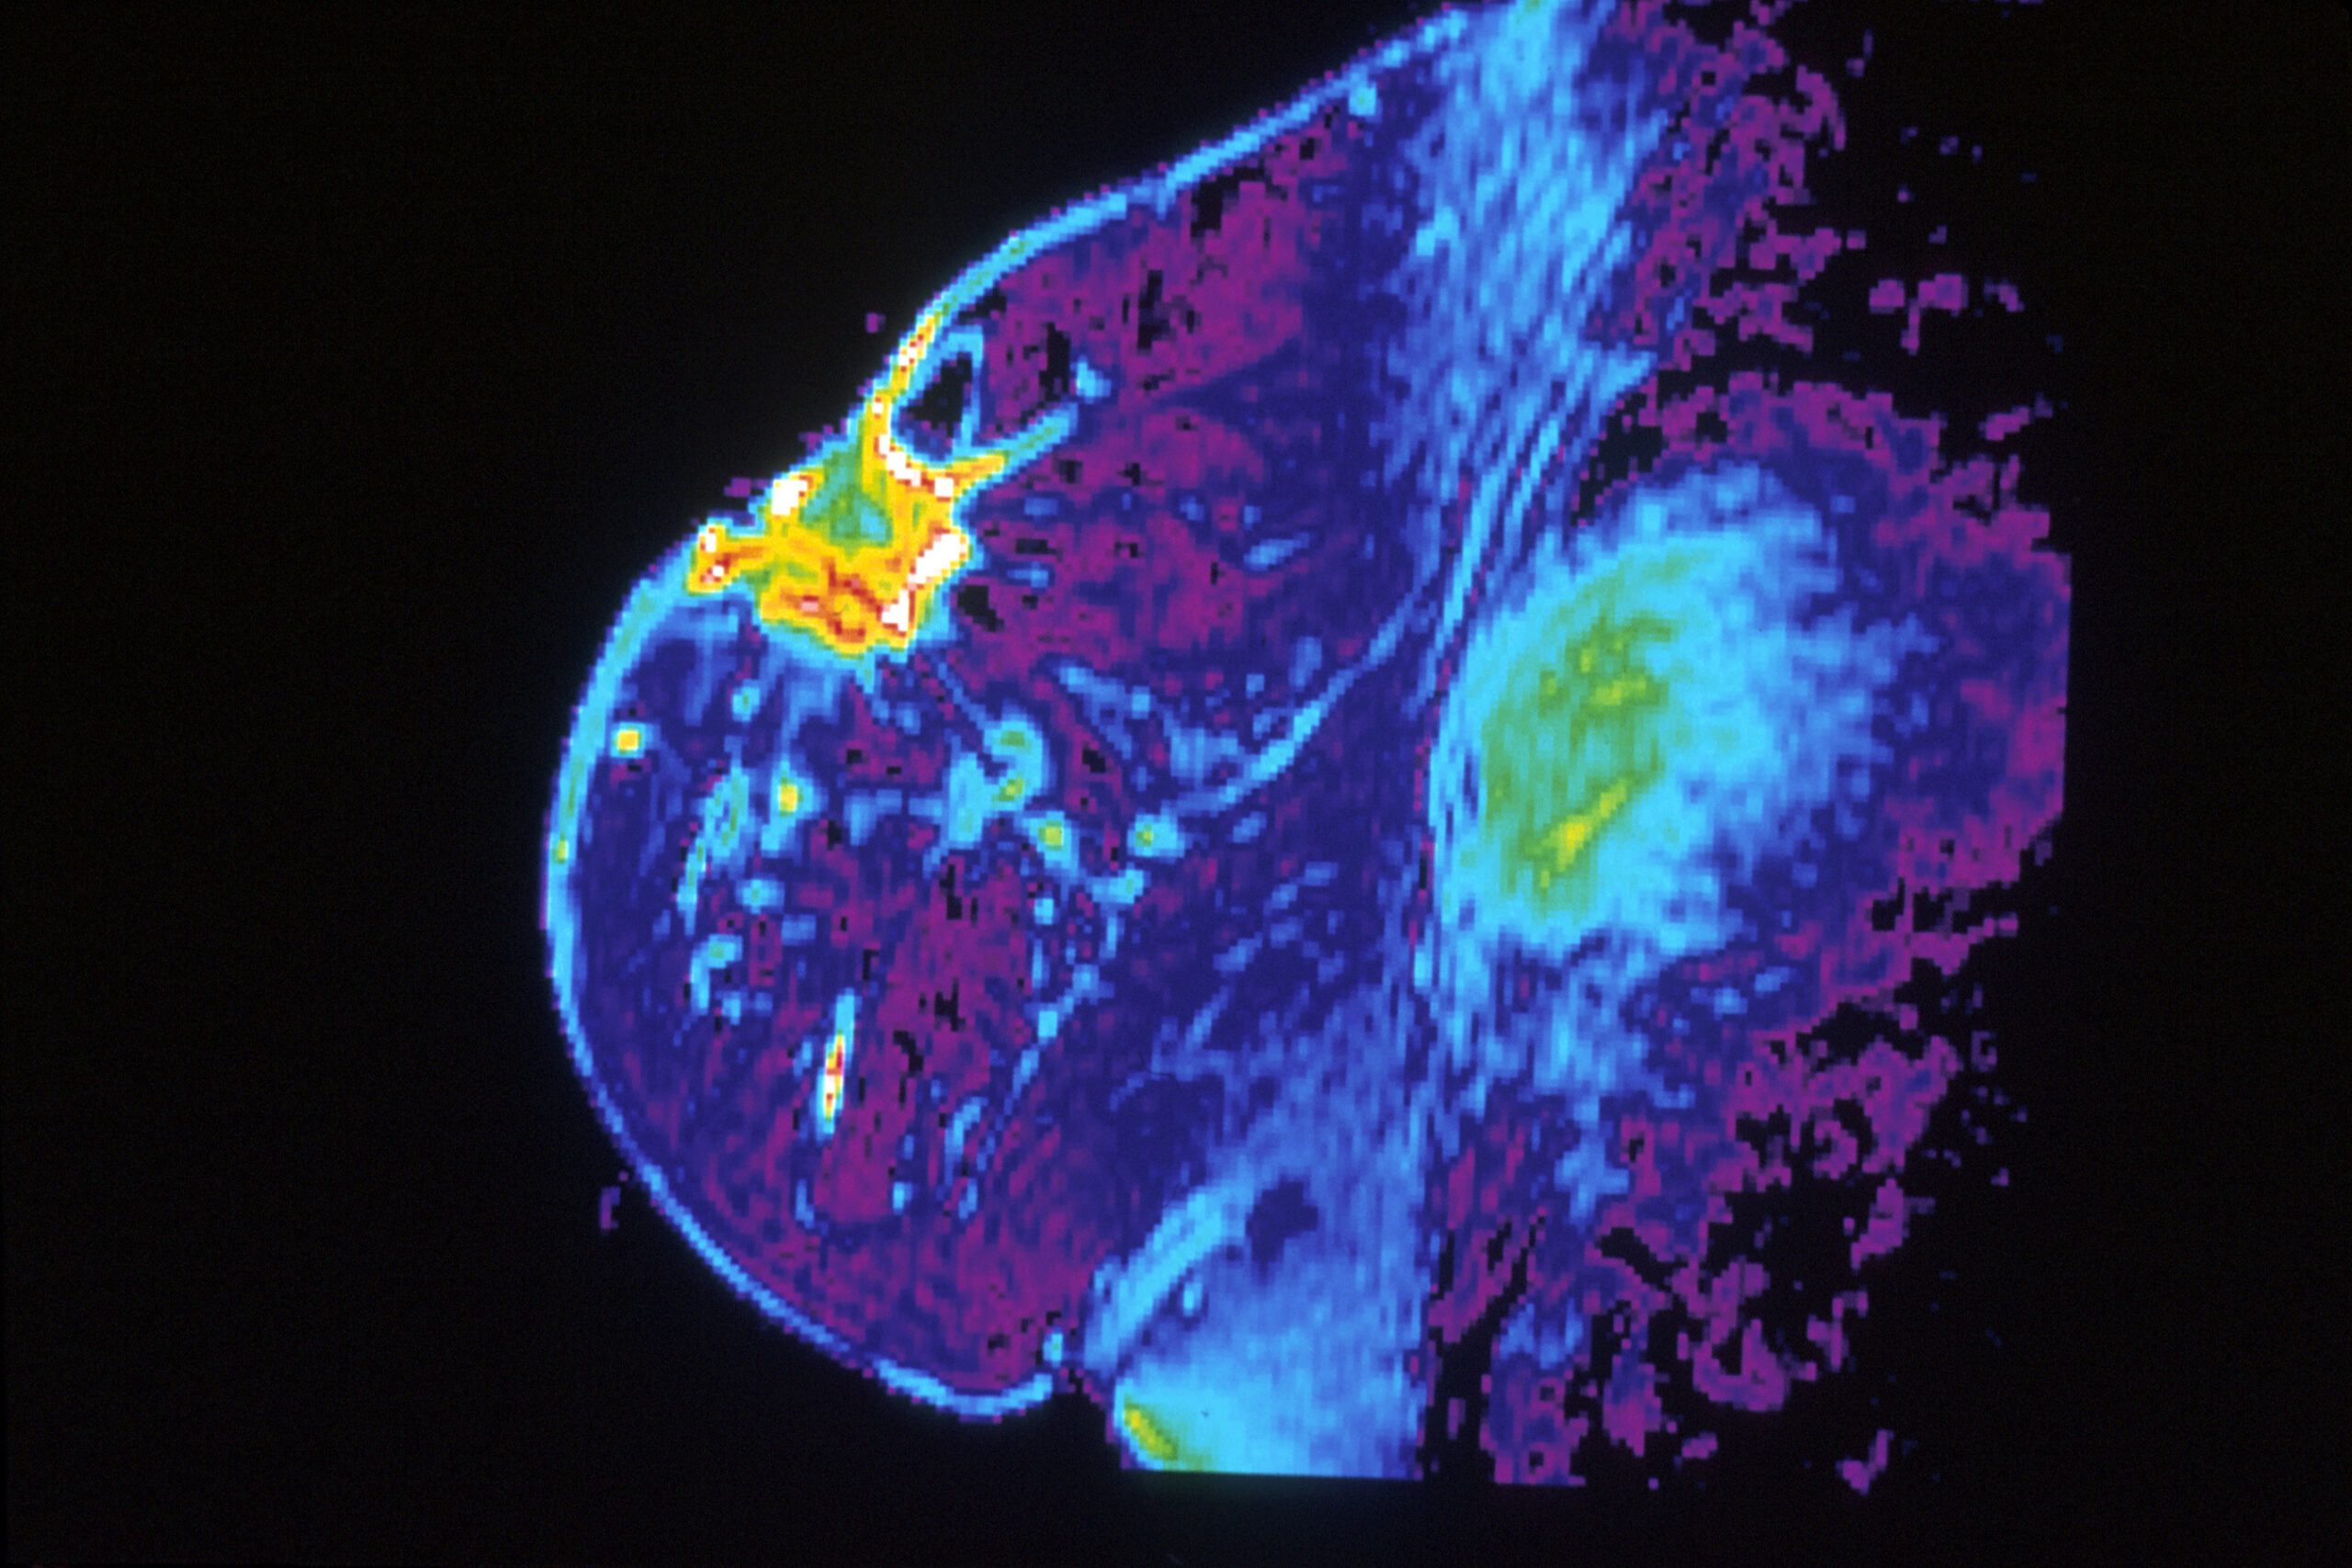

False-color MRI images like these aren't typically used for breast cancer screening, but they can provide more detailed images of the breast, which is useful for high-risk patients. National Cancer Institute via Wikimedia Commons